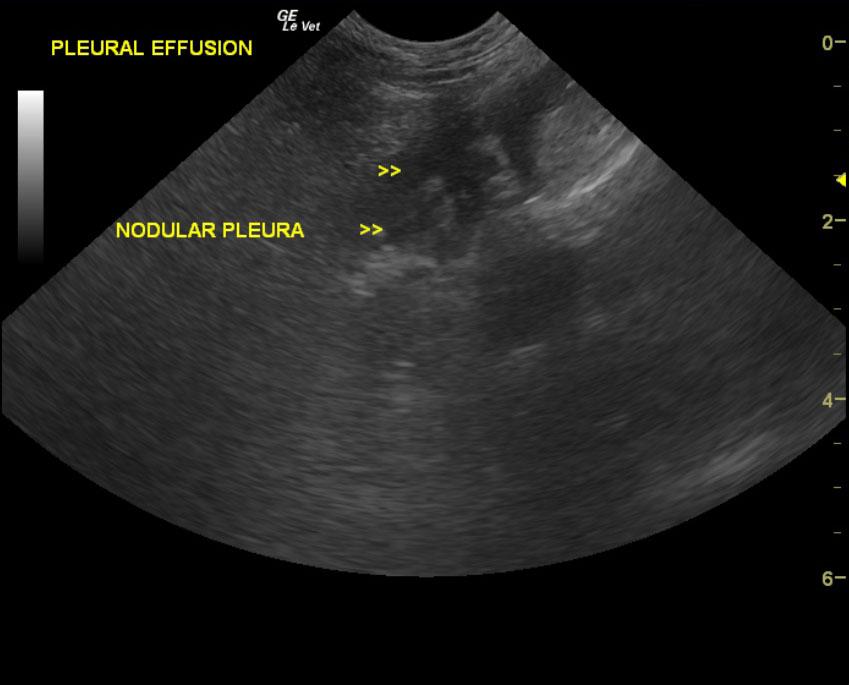

A 12-year-old FS Kerry Blue Terrier dog was presented for evaluation of poor appetite and not being himself. He also had a history of periodic lethargy.